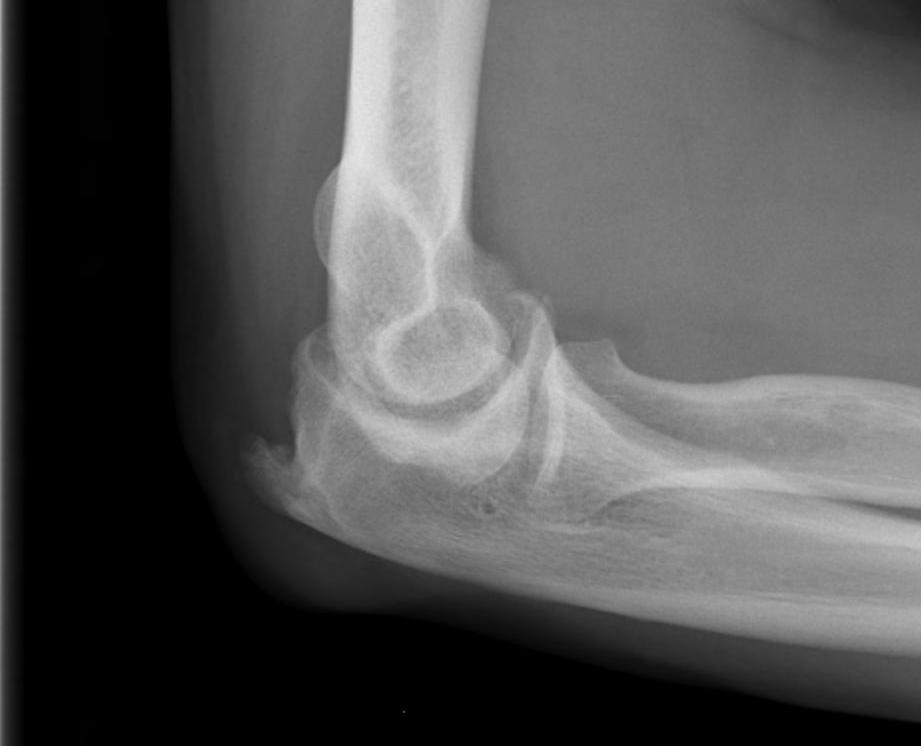

X-ray

Early stage

- preserved radiocapitellar and ulnohumeral joints

- osteophytes of the olecranon and coronoid

Lateral xray demonstrating olecranon and coranoid osteophytes